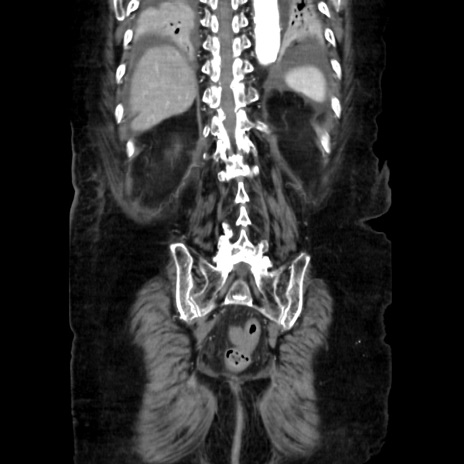

症例40(冠状断像)

【症例】90歳代女性

【主訴】腹痛・嘔吐

【現病歴】 食欲低下、嘔吐があり昨日他院受診。肺炎と診断され入院となる。入院後より腹部全体に圧痛あり。胃管留置され経過みていたが、症状持続するため、

当院転院となる。

【既往歴】胸椎圧迫骨折、胆石症

【身体所見】腹部:中央に激痛あり、圧痛あり、反跳痛不明

【データ】WBC 17100、CRP 18.82

冠状断像